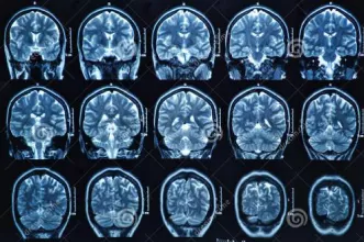

MRI也就是磁共振成像,屬于斷層成像的一種,它是利用磁共振現(xiàn)象從人體中獲得電磁信號(hào),并重建出人體信息。通過(guò)檢查可獲得橫斷面、矢狀面、冠狀面的影像,空間分辨率高,是神經(jīng)系統(tǒng)、脊柱脊椎部分檢測(cè)的第一選擇。

無(wú)論是DR還是CT,由于對(duì)部分軟組織的分辨率不足,所以軟組織疾病的排查便成了它們的短板,而磁共振的長(zhǎng)處恰恰就是清晰顯示軟組織疾病,對(duì)于膀胱、直腸、子宮及關(guān)節(jié)肌肉的檢查優(yōu)于CT。MRI適用于神經(jīng)系統(tǒng)病變、心血管系統(tǒng)、胸部病變、全身軟組織病變等。